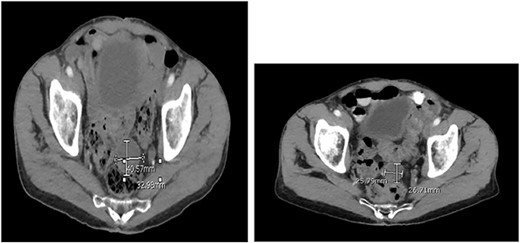

Two months after the tumor was grossly resected and 1 month into Imatinib treatment, the patient presented to the Emergency Department with complaint of abdominal discomfort, constipation and nausea. CT abdomen and pelvis noted mid small bowel distention, suggestive of partial small bowel obstruction with mild ascites. Importantly, a mass-like focus measuring 5 × 3.8 cm was found in the pelvis anterior to the rectosigmoid junction (Fig. 3). A nasogastric tube was subsequently placed and the patient was administered empiric antibiotics. Considered a failure of conservative management, the patient was taken to the operating room again for an exploratory laparotomy, lysis of adhesions and debulking of the mass. The patient tolerated the procedure well with no complications. The patient maintained a typical postoperative course and was discharged with oncological follow-up and continued Imatinib treatment. On 2 and 4 months follow-up CT, the pelvic mass measured 4.1 × 3.3 and 2.6 × 2.7 cm (Fig. 4), respectively.

CT abdomen and pelvis at (A) 2- and (B) 4 months follow-up. The pelvic mass measured 4.1 × 3.3 and 2.6 × 2.7 cm, respectively.